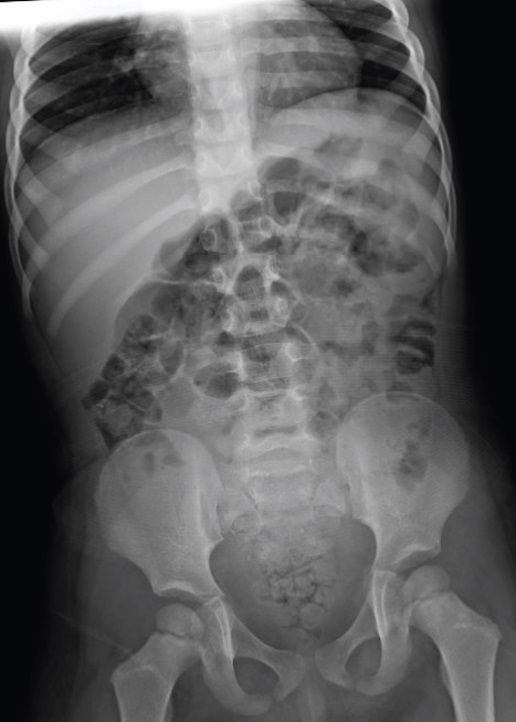

lead poisoning xray jan 2024